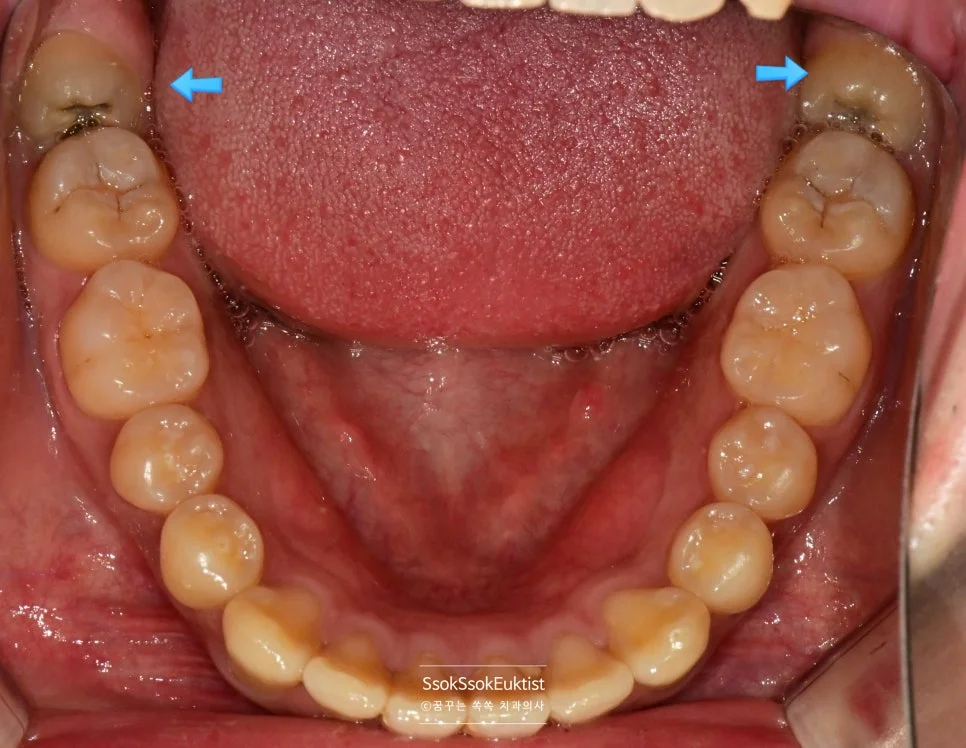

하악 구강 사진 매복 사랑니

아래 사랑니 — 앞 치아에 걸려 매복된 상태

위 두 개의 사랑니는 올바르게 났고, 아래 두 개는 앞 치아에 걸려 매복되어 있는데요.